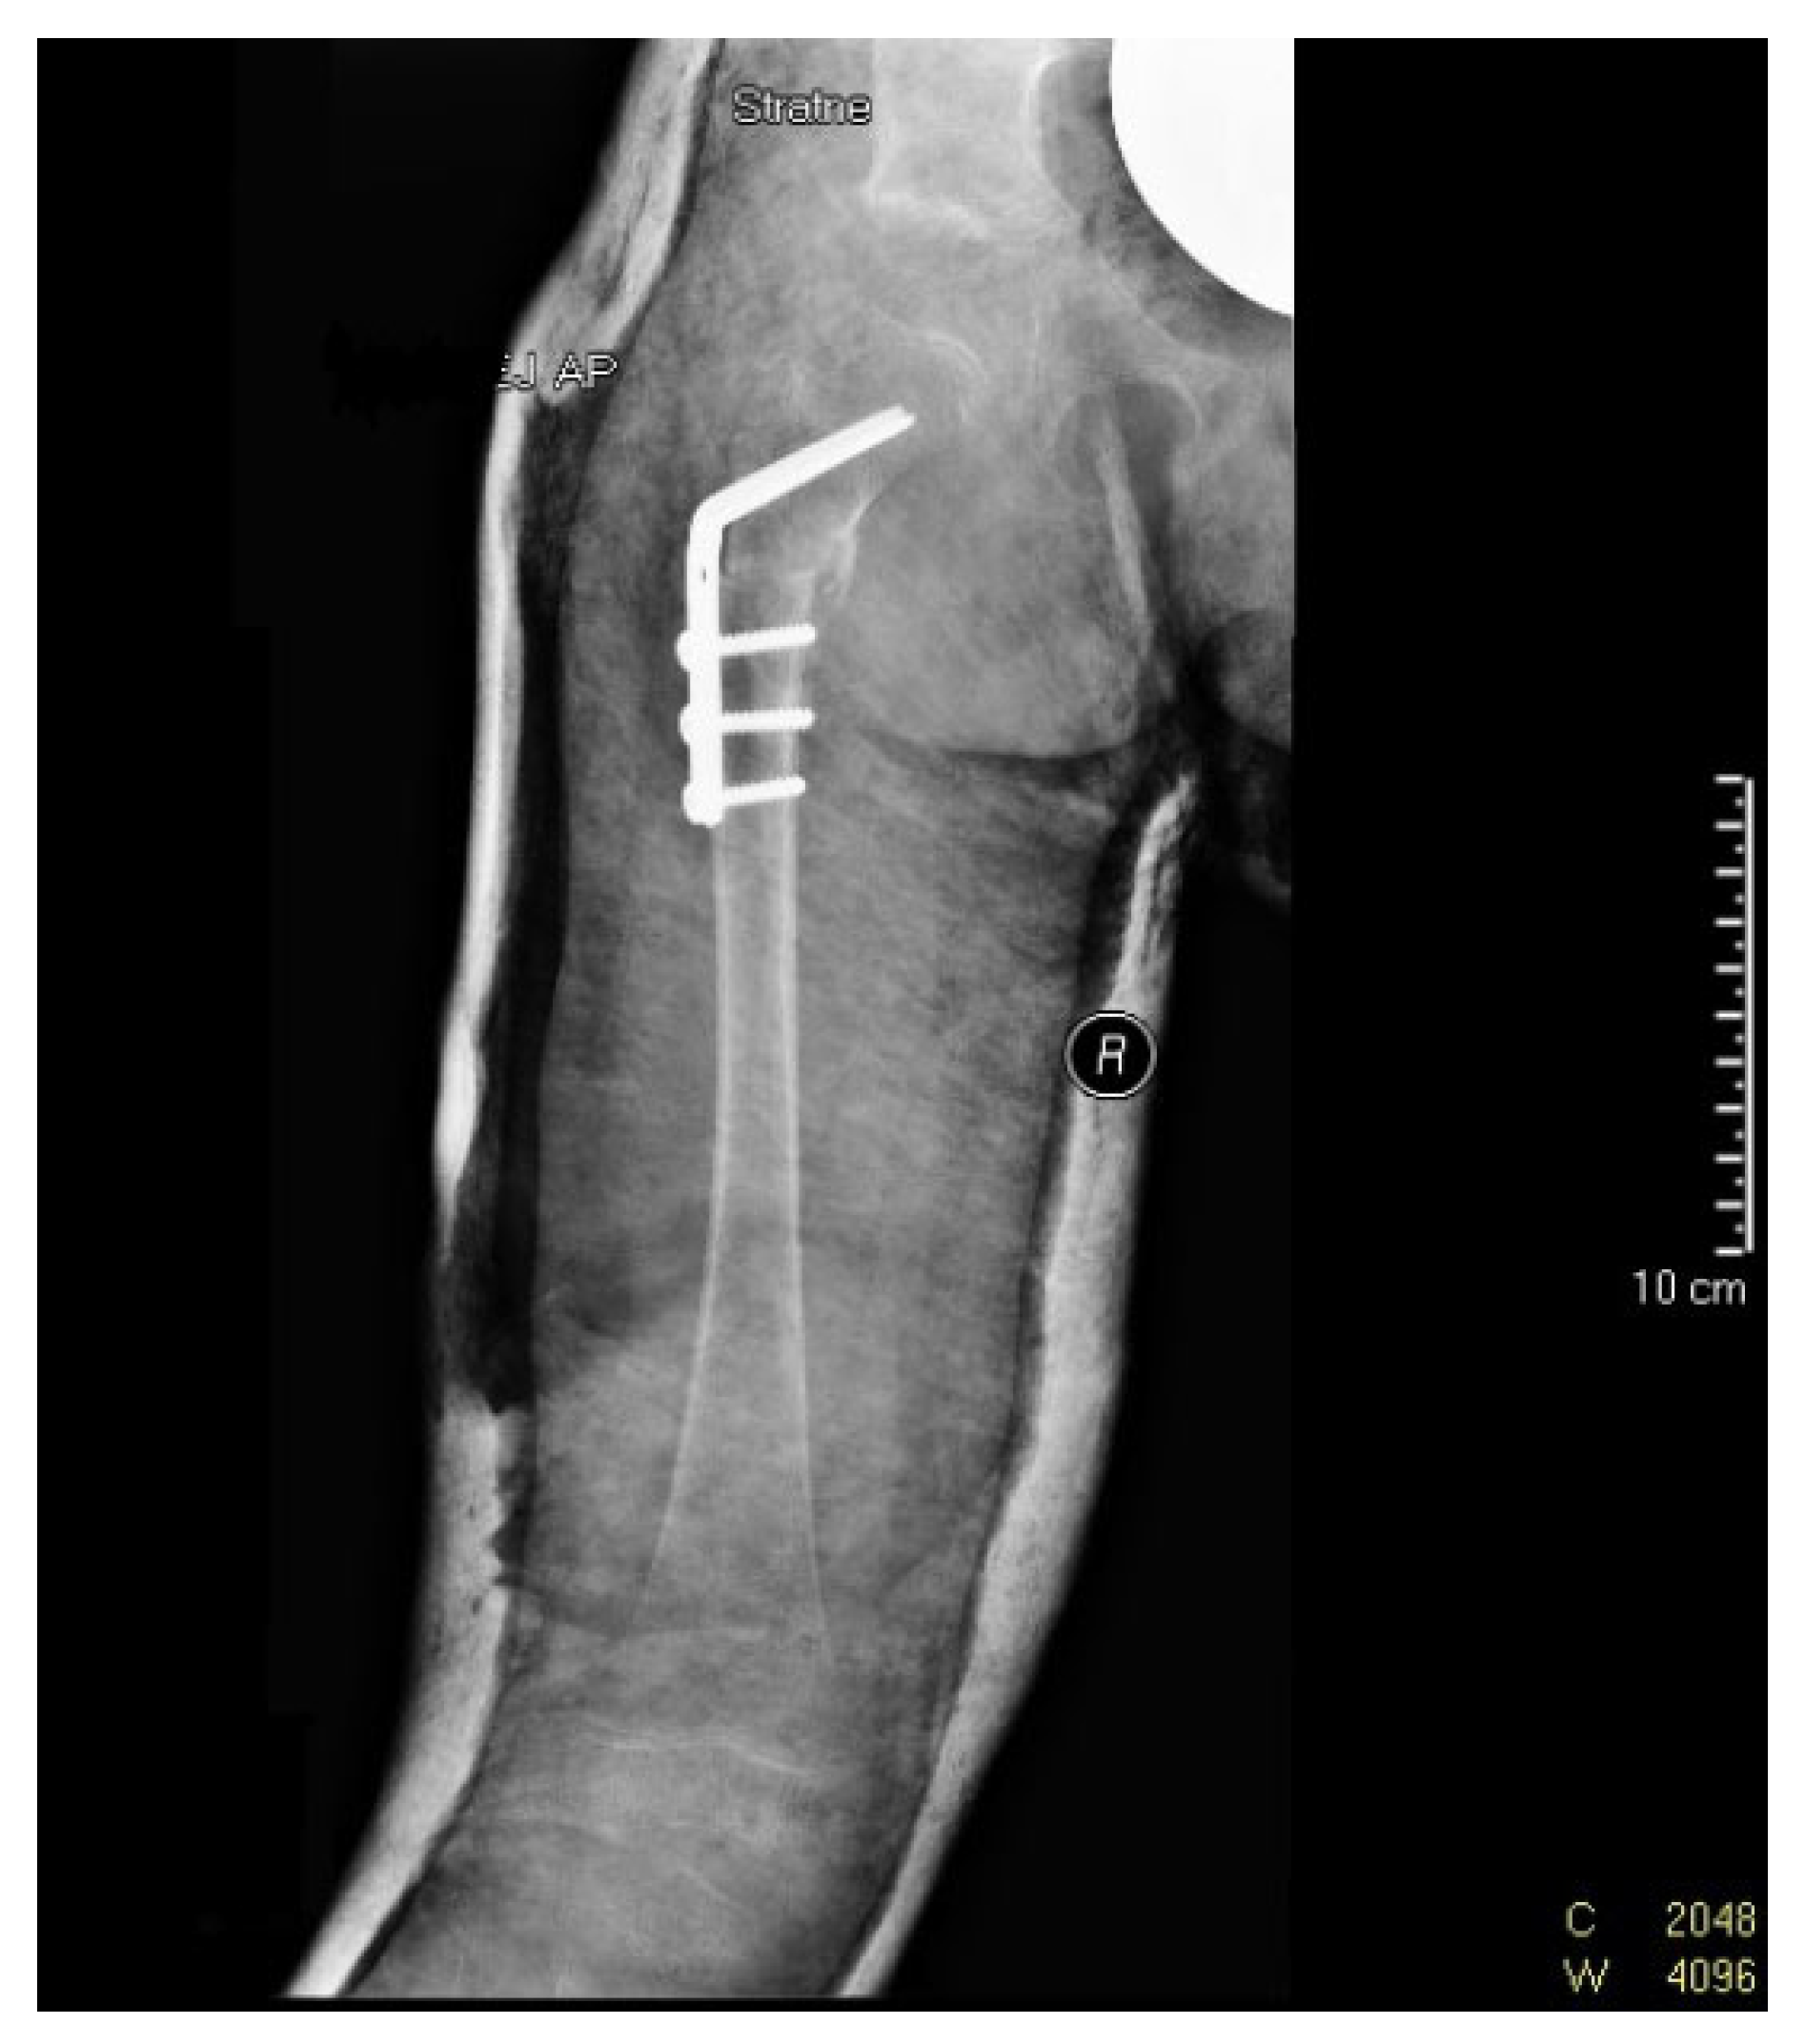

Due to persistent radiological evidence of subluxation in the right hip joint, at the age of 4.5, another pelvis osteotomy was performed using the Salter method. At the age of five, all metallic osteosyntheses were surgically removed and a pelvic computed tomography (CT) scan was performed (Figure 4). The next (third) surgery involving varus direction and de-rotative osteotomy on the proximal part of the right femur was performed on the girl at age 6 (Figure 5).

Figure 5. X-ray scan following varus and de-rotative osteotomy on the proximal part of the right femoral bone (at 6 years of age).